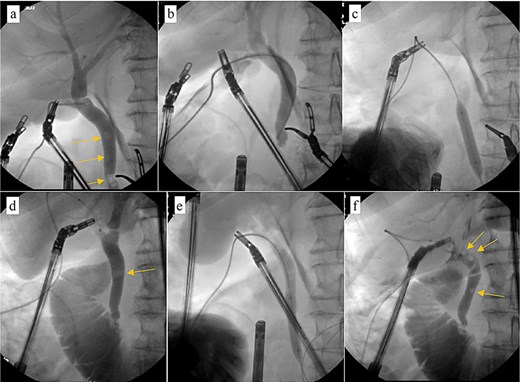

Computed tomography (CT) in the ER showed normal gastric bypass anatomy with moderate colonic stool burden. Negative for biliary pathology. Follow up ultrasound showed cholelithiasis without evidence of acute cholecystitis. A confirmatory HIDA showed normal filling of the gallbladder with rapid clearance into the small bowel and ejection fraction of 62% (Fig. 1).

HIDA scan showing normal gallbladder filling and rapid emptying of nucleotide contrast in the SB following administration of CCK.

Pericholecystic fluid (arrows) and positive sonographic murphy sign present on the post-HIDA ultrasound (right) that was not previously seen on the pre-HIDA ultrasound on admission (left).